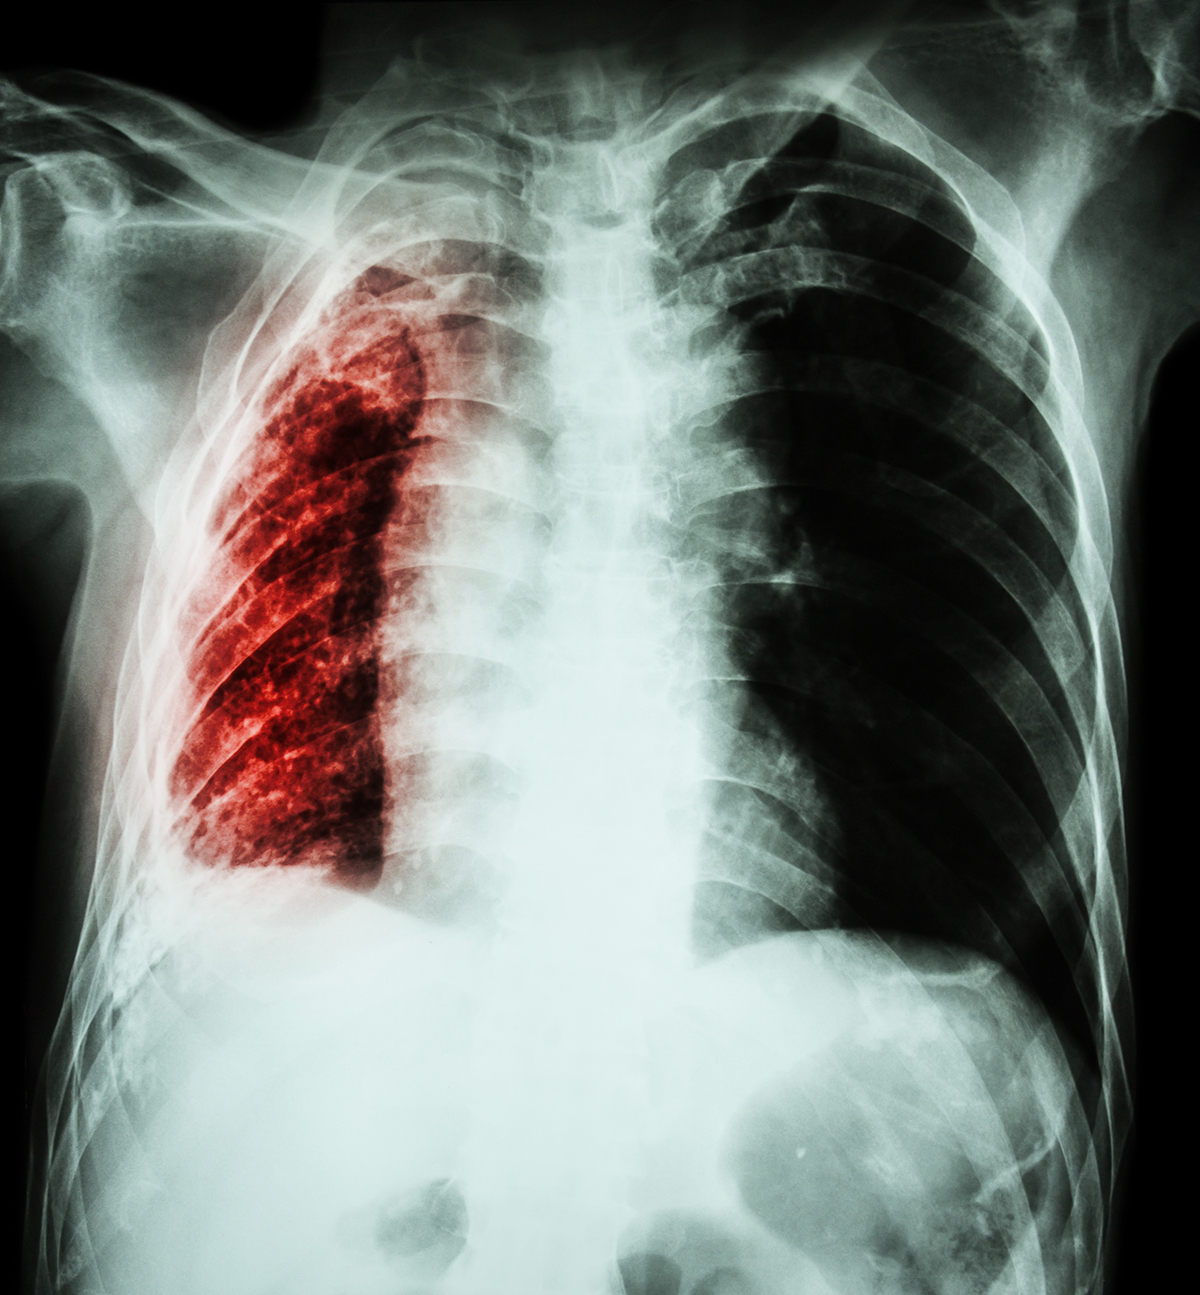

Снимок легких при туберкулезе является важным методом диагностики этого заболевания. На рентгеновских снимках можно увидеть изменения в легких, которые свойственны туберкулезу.

Рентген легочное кровотечение туберкулез

Фотографии снимков легких при туберкулезе

В данной статье представлены многочисленные фотографии снимков легких при туберкулезе, чтобы помочь вам понять, как выглядят изменения легких на рентгеновских снимках при этом заболевании.